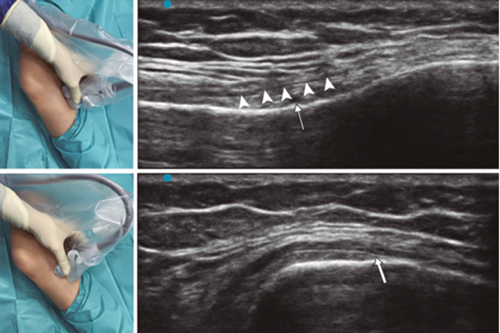

Fig. 3. Sonoanatomy and technique for performing superior medial genicular nerve block (SMGN). The transducer is located on the distal long axis of the femur and once the position of the SMGN (asterisks) is known, the probe is rotated 90 degrees to obtain a view of the femur short-axis (don't forget to keep the same depth that we find the SMGN on the long axis). VM (vastus medialis).

In order to achieve a correct location of anatomical landmarks by ultrasound we must place the patient in supine position with the knee flexed and a pillow under the popliteal fossa (14,16,19).

Fig. 4. Sonoanatomy and technique for performing inferior medial genicular nerve block (IMGN). The transducer is located on the proximal long axis of the tibia and we identify the vasculonervious package of the IMGN (arrow) just below medial collateral ligament (arrowheads). Then the probe is rotated 90 degrees to obtain a short-axis view of the tibia (don't forget to keep the same depth as the IMGN found on the long axis).

After performing knee asepsis/antisepsis, surgical field placement, and the sterile sheath of the high frequency linear transducer, we proceed to locate the SMGN (Figure 3). Placing the probe in a coronal plane on the inner face of the knee, we slide it cranially to visualize the junction of the metaphysis to the femoral diaphysis and the superior medial genicular artery/nerve (ASMGN), usually located near the periostium of the femur (if this neurovascular structure is not found, the junction between metaphysis and femoral diaphysis is taken as a reference). The mid-point of the transducer corresponding to ASMGN is then marked on the skin and the transducer is rotated to be placed in the transverse or axial plane to view ASMGN on the short axis (if this structure is not visible, confirm that we are at 50 % depth of the femur). In this cross-section the needle of the TRF is advanced in plane from anterior to posterior toward the ASMGN or to a depth of 50 % of the thickness of the femur. Finally, the transducer is rotated 90° again, leaving it in a coronal plane to check that the needle tip is near the ASMGN or the junction of the metaphysis and femoral diaphysis (14,16,19).

To locate the IMGN (Figure 4), we placed the transducer in a coronal plane on the inner face of the knee, sliding it caudally to identify the diaphysis junction with the tibial metaphysis and the inferomedial genicular artery/nerve (AIMGN). And we repeat the same steps we used for SMGN. If the AIMGN is not found, the reference to be taken shall be the depth of 50 % of the thickness of the tibia (14,16,19).

To locate the SLGN, the patient must be supine with the lower limb in internal rotation, obtaining good exposure to the lateral side of the thigh. We place the linear transducer in a coronal plane on the lateral side of the knee, slide it in a cranial direction to visualize the junction of the metaphysis with the femoral diaphysis and the superior lateral genicular artery/nerve (ASLGN), and repeat the same steps that we use for SMGN (14,16,19).